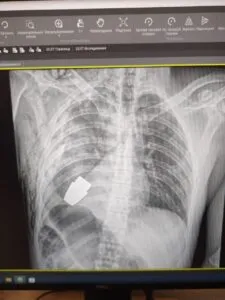

Hirurzi su uklonili eksplozivno sredstvo koje se nalazilo tik ispod srca ozlijeđenog vojnika, dok su se dva sapera pobrinula da operacija bude provedena sigurno, kazala je Hanna Maliar, zamjenica ukrajinskog ministra odbrane, koja je objavila fotografiju na kojoj se vidi rendgenska snimka granate u tijelu vojnika.

“Vojni doktori su izveli su operaciju uklanjanja VOG granate, koja se nije raspala, iz tijela vojnika”, napisala je u objavi na Facebooku.

Operacija je izvedena bez korištenja elektrokoagulacije - uobičajene metode za kontrolu krvarenja tokom operacije - jer bi “granata mogla detonirati u svakom trenutku”, rekao je Maliar.